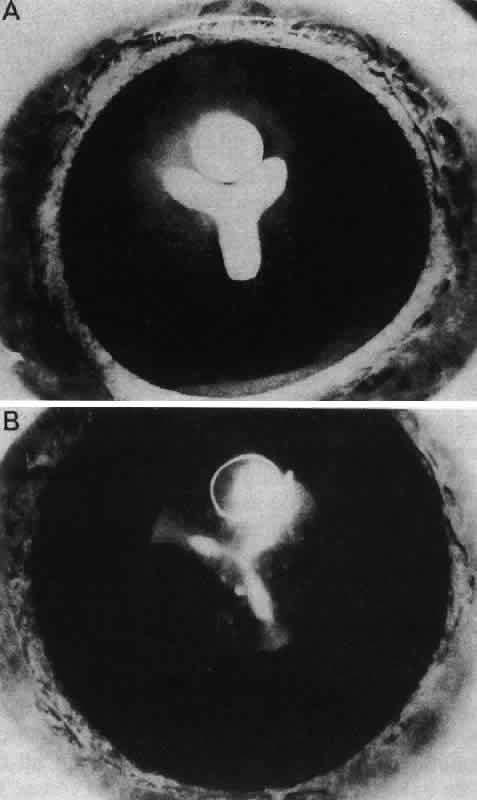

Retrolental Fibroplasia

Persistence of the hyaloid artery and the tunica vasculosa lentis may be associated with a pseudoglioma (pseudoretinoblastoma), an extensive connective tissue proliferation behind the lens. Two primary types, both rare, have been reported. One, retrolental fibroplasia, is primarily associated with infants born more than 8 weeks prematurely (i.e., before complete regression of the tunica vasculosa lentis) and is almost always bilateral. This may occur spontaneously or be associated with oxygen therapy in premature infants.175 Another type of pseudoglioma, persistent hyperplastic primary vitreous, may also occur as a unilateral condition in full-term infants. Dehiscence of the lens capsule is usually seen posteriorly, and the lens is sometimes cataractous.